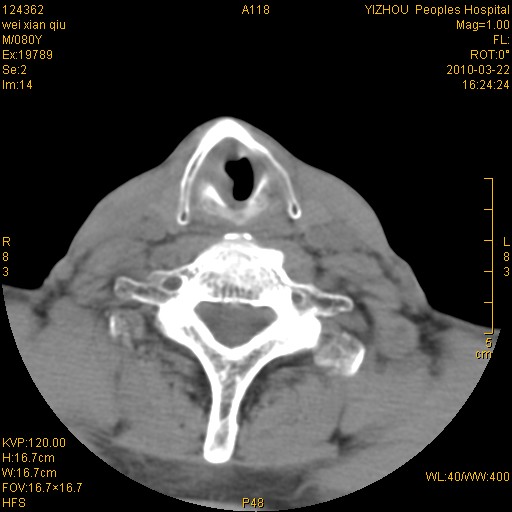

标题: CT25263:喉部占位?

男,80岁.声嘶三月余.

喉前庭右侧壁明显增厚,并见向内突出的软组织密度新生物,表面光滑,其后方软组织层次尚清晰,多考虑:喉部乳头状瘤!建议喉镜并病检!

右侧声们下区新生物